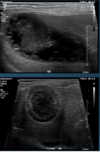

What is shown in these images?

ultrasound of the gall bladder:

-top: anechoic bile

-bottom: sludge (normal in dogs)